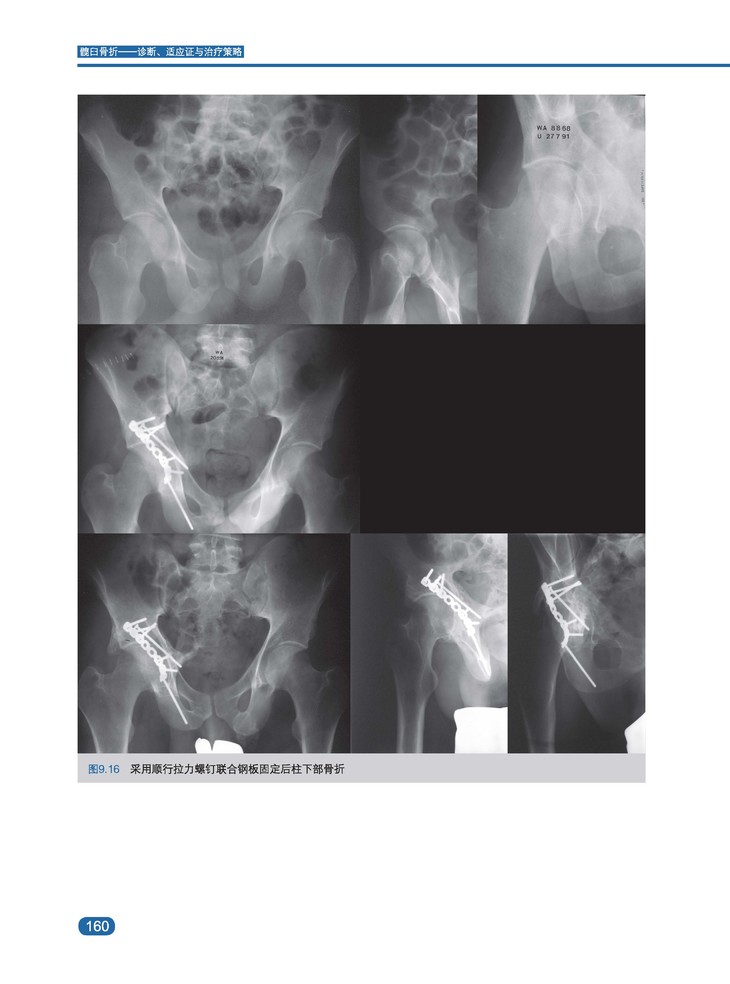

内容简介:髋臼骨折的罕见性和骨折类型的多样性使骨科医生面临巨大挑战。髋关节与周围神经血管结构密切相关,因此,髋关节手术需要特别小心,以保持长期的生物力学稳定性并延缓中青年患者创伤后骨关节炎的发展。本书旨在为骨科医生提供诊断和评估髋臼骨折的策略,适应个体化治疗的需求,采取解剖学引导下的恰当的复位和固定方法。全书图文并茂,基础部分从髋臼外科解剖、生物力学、影像学诊断、髋臼骨折分型、流行病学、治疗适应证及计划、手术入路等方面进行详细讲解。临床部分,按照Letournel分型对各类型髋臼骨折分别从骨折特点、影像学标准、病理生物力学、合并伤、髋关节稳定性、骨折生物力学、适应证、内固定技术、预后等方面结合最新临床数据加以系统分析阐述。此外,结合解剖学及影像学系统介绍了髋臼特殊螺钉的定位及操作技巧。最后,本书详细介绍了老年及儿童髋臼骨折的特点、分型、治疗、预后,以及异位骨化及血栓栓塞等并发症的发生、预防及预后问题。

· 400余幅高质量全彩示意图、影像图、术中图片,全方位展示髋臼骨折的诊断、适应证与治疗策略。